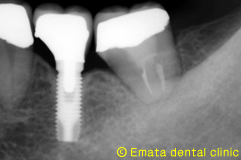

1本の歯を失った場合は、通常はブリッジになることが多いですが、隣の歯を削る大きな欠点があります。その他の治療としてインプラント治療がありますが、歯牙移植 という治療も選択枝にはあるわけです。

移植治療は、適応症が限られるためケースとしてはそれほど多いとは言えませんが、いろいろな面でインプラント同等、場合によってはそれ以上の効果があると考えています。

患者様は左下のブリッジの土台が腫脹して来院されました。大きな根の病気・歯根歯折も疑われます。抜歯の適応です。左下は2歯がなくなり、患者様の希望と適応症から、2歯欠損に移植とインプラントを両方行う治療計画にしました。

親知らずを移植歯に使用しました。大きさ、根の形態、歯根膜の状態、すべてに適応症の歯です。 |

| インプラント手術。歯肉の移植も行いました。 | |

| 歯牙移植・インプラントのどちらが有利かは診査・診断をしっかりおこない適応症を見極めることです。 | |